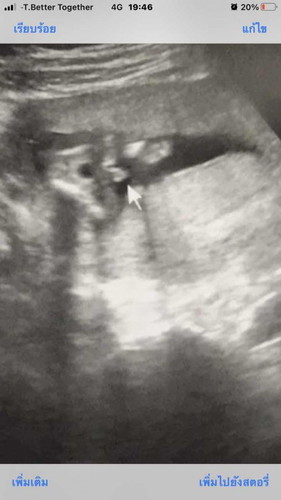

นี้คุณหมอบอก มีแหลมออกมาเลยบอกว่าเป็นผู้ชาย ซาวด์ตอน16วีค 5จ้า แม่ๆที่ซาวด์ได้ลูกลายเป็นแบบนี้ไหมค่า

ของพี่ 17 สัปดาห์คะผช จู๋โด่เลย